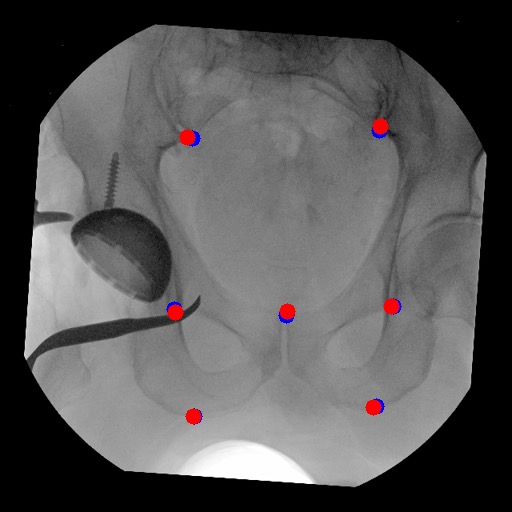

We compared the performance of our method to three different methods: a baseline U-Net, U-net with training set augmentation, and U-net with both training set augmentation and label augmentation. As shown in Table 1, in comparison to all baseline methods, our training method performs better: the mean RMSE across datasets has decreased from over 100 to less than 4. Also, we have done random rotation of a maximum of 20 degrees for the training set augmentation, and it did not work on both baseline U-net and U-net with label augmentation. We plot the results in Figure 1.